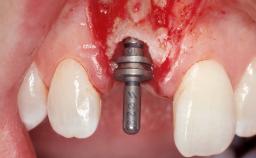

Late Flapless Placement of an Implant in a Maxillary Left Central Incisor Site

Placement Protocol Early or late implant placement

Bone Volume Deficient horizontally, requiring prior grafting

Bone Augmentation Horizontal|Staged